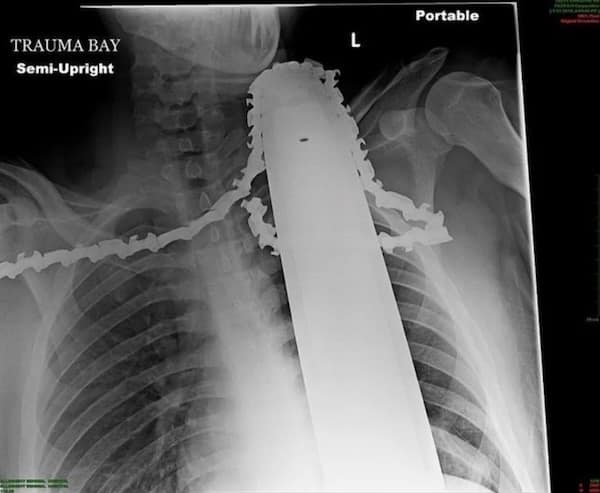

Weird xray photos

I used to think that nothing could surprise me anymore—until I stumbled upon some weird x-ray photos that made me reconsider my stance on human ingenuity (or lack thereof). Apparently, some people have a knack for getting objects lodged where they absolutely shouldn’t be. If you’ve ever wondered how not to use everyday items, these images might provide some unintended guidance.

This collection showcases 31 bizarre x-ray images that defy logic and anatomy textbooks alike. Each photo reveals unexpected objects making cameo appearances inside the human body, turning medical imaging into a gallery of the absurd. From common household items inexplicably found in unusual places to anomalies that would leave even seasoned doctors scratching their heads, these images offer a perplexing glimpse into the more “creative” side of medical emergencies. They highlight the intersection of curiosity, misadventure, and perhaps a dash of poor decision-making, all captured through the lens of radiology.